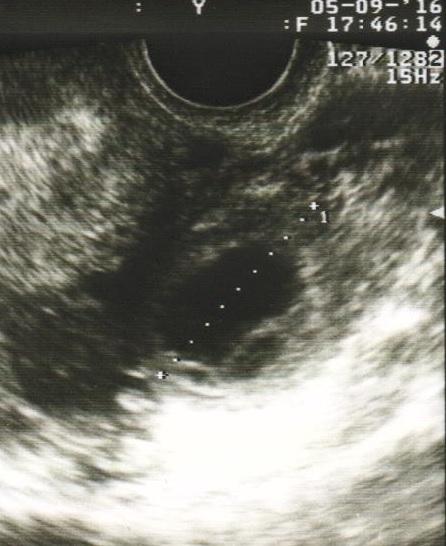

@kakatulik @simisk ahojte, tak podavam spravy 🙂... kedze dnes som mala ist na hysteroskopiu, tak som volala lekarovi, ze mi zatial nedosla MS a mam pozitivne testy a on, ze ak mozem, mam ihned prist...tak nam urobil malu fotku 😉... mame 12mm, nariadeny maximalny kludovy rezim a kontrola o tyzden, tak dufam, ze vsetko bude o.k.

@kakatulik dakujeeeem 🙂 ...lebo mam krvnu zrazeninu a 3 cysty ☹ , ale vraj tie cysty by sa mali vstrebat a malo by to byt v pohode, vraj to moze byt zo stimulacie, ale ak by sa nieco dialo, tak mu mam okamzite volat a prist zbalena do nemocky, preto mam aj pre istotu kontrolu o tyzden v utorok, lebo potom ide na kongres a chce mat istotu 😉